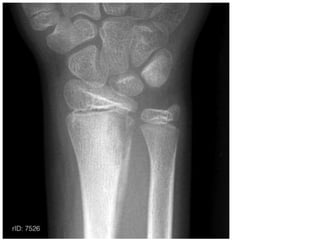

Colles Fracture

Colle’s fracture-

• Radius gets fractured about 2 cm above its lower end

due to fall on outstretched hand

Smith’s fracture- Reverse of Colle’s fracture

• If distal fragments gets displaced anteriorly

Colle’s fracture- • Radiusgets fractured about 2 cm above its lower end due to fall on outstretched hand Smith’s fracture- Reverse of Colle’s fracture • If distal fragments gets displaced anteriorly